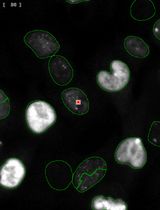

利用自动化图像细胞计数法简化量化p-γ-H2AX焦点分析,以评估暴露于FLASH辐射的小鼠黑色素瘤及黑色素细胞共培养中的DNA损伤

Streamlined Quantification of p-γ-H2AX Foci for DNA Damage Analysis in Melanoma and Melanocyte Co-cultures Exposed to FLASH Irradiation Using Automated Image Cytometry

In response to DNA-damaging physical or chemical agents, the DNA damage repair (DDR) pathway is activated in eukaryotic cells. In the radiobiology field, it is important to assess the DNA damage effect of a certain irradiation regime on cancer cells and compare it to the effect on non-transformed cells exposed to identical conditions. The first step in the DNA repair mechanism consists of the attachment of proteins such as the phosphorylated histone γ-H2AX (p-γ-H2AX) to DNA double-strand breaks (DSB) in the nucleus, which leads to the formation of repairing foci. Therefore, imaging methods were established to evaluate the presence of foci inside the nucleus after exposure to DNA-damaging agents. This approach is superior in sensitivity to other methods, such as the comet assay or the pulsed-field gel electrophoresis (PFGE), that allow direct detection of cleaved DNA fragments. These electrophoresis-based methods require high ionizing radiation dosages and are difficult to reproduce compared to imaging-based assays. Conventionally, the number of foci is determined visually, with limited accuracy and throughput. Here, by exploring the effect of laser-plasma accelerated electrons FLASH irradiation on cancer cells, we describe an image cytometry protocol for the quantification of foci with increased throughput, upon large areas, with increased precision and sample-to-sample consistency. It consists of the automatic scanning of fluorescently labeled cells and using a gating strategy similar to flow cytometry to discriminate cells in co-culture based on nuclei elongation properties, followed by automatic quantification of foci number and statistical analysis. The protocol can be used to monitor the kinetics of DNA repair by quantification of p-γ-H2AX at different time points post-exposure or by quantification of other DNA repair proteins that form foci at the DNA DSB sites. Also, the protocol can be used for quantifying the response to chemical agents targeting DNA. This protocol can be performed on any type of cancer cells, and our gating strategy to discriminate cells in co-culture can also be used in other research applications.